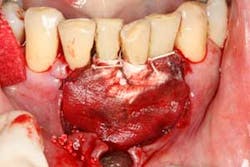

Figure 1: Full-mouth series taken in 2010, showing severe bone loss in the posterior maxillary molar and mandibular anterior incisor area.

At presentation, Martin was in his fifties with a medical history significant for controlled hypertension with no known food or drug allergies. He had been lackadaisical with his dental care in the past because of his busy schedule, but he was motivated to get his hygiene and treatment under control. He denied a history of smoking/alcohol/drug use. Based on his full-mouth series (figure 1) and clinical presentation, Martin had generalized, moderate bone loss with localized, severe bone loss in the posterior maxillary right and left quadrants (figures 2a and 2b) as well as the mandibular anterior incisor area (figure 3).